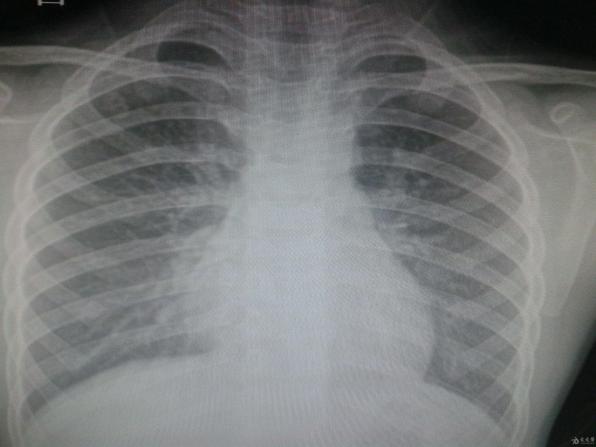

如果不搞一個(gè)話我就把你曝光了,以后在發(fā)現(xiàn)這個(gè)情況我就把你按照胸片曝光出來,你不怕把東西用給我刷,我就把你按到辦,然后還敢等你一。第二張拍的胸片,被醫(yī)生將肋骨骨折的部位曝光為白色,隱瞞肋骨骨折的...